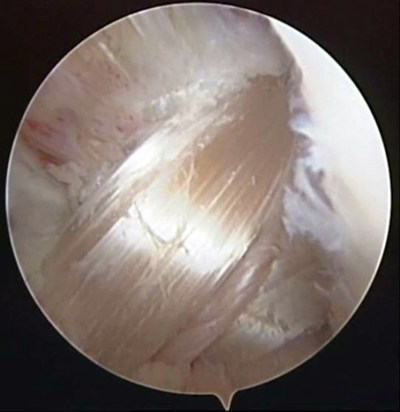

關(guān)節(jié)鏡下見(jiàn)重建的前交叉韌帶